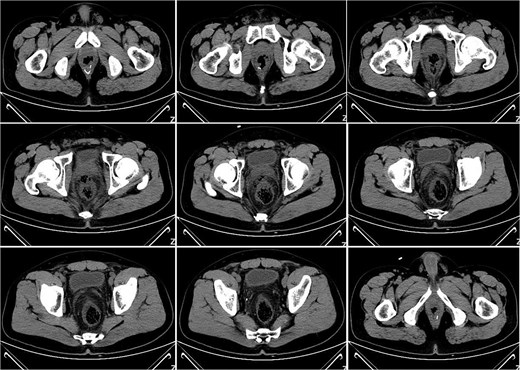

On postoperative Day 10, a repeat complete blood count showed a white blood cell count of 9.74 × 109/l and a neutrophil percentage of 69.5%. The patient’s temperature ranged between 36.4 and 37.4°C, and abdominal discomfort was partially alleviated. A follow-up pelvic CT scan revealed a breach in the anterior rectal wall with gas density shadows communicating with the surrounding area, accompanied by filamentous exudate density shadows and multiple gas density shadows (Fig. 2). These findings indicated rectal wall edema and anterior wall perforation with surrounding infection. Anorectal examination revealed a 0.5 × 0.5 cm ulcerative lesion at the 5 o’clock position of the anastomosis site in the knee–chest position. This was considered rectal perforation secondary to anastomotic dehiscence. Given the absence of peritoneal irritation signs and normalization of the white blood cell count, a conservative treatment plan was adopted after discussion with the patient. This plan involved continuing anti-infective treatment with intravenous cefoperazone sodium and sulbactam sodium.